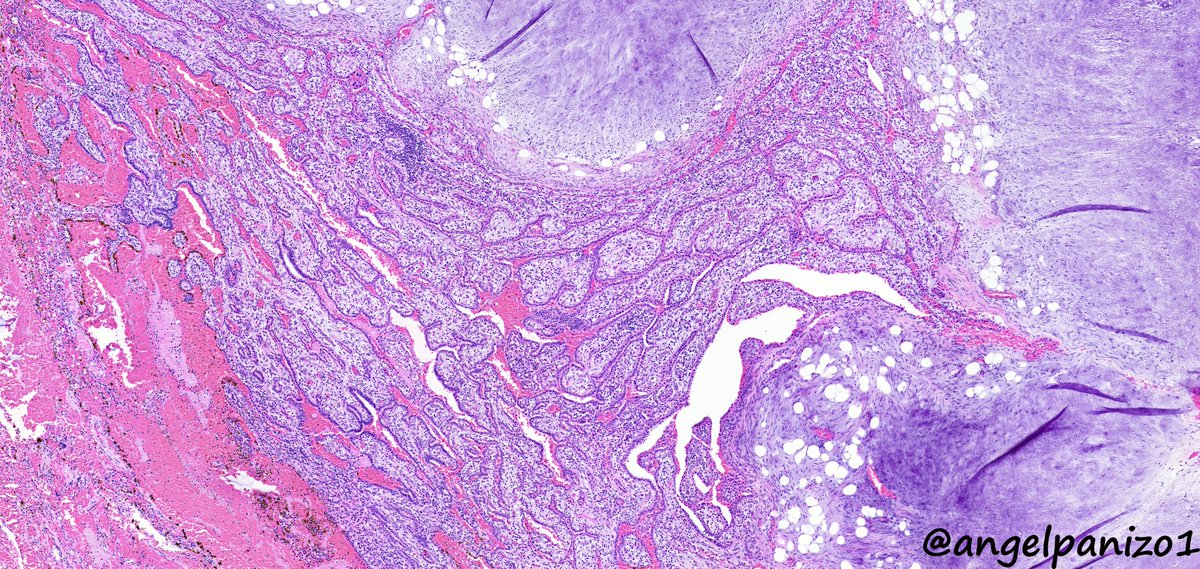

Incidental lung tumor... pulmonary hamartoma with unusual morphology?... what is your opinion? (2⃣) #PathTwitter #pulmpath @smlungpathguy @SansanoValero @yro854 @natasharekhtman @mkbaine @atman_ci @Path_Matt

angelpanizo1's tweet image. Incidental lung tumor... pulmonary hamartoma with unusual morphology?... what is your opinion? (2⃣) #PathTwitter  #pulmpath @smlungpathguy @SansanoValero @yro854 @natasharekhtman @mkbaine @atman_ci @Path_Matt